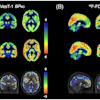

They found that F-18 FDG-PET/CT can be useful in breast cancer management, including initial staging, assessing neoadjuvant systemic treatment response, assessing treatment response in the metastatic setting, searching for loco-regional or metastatic recurrence, and re-staging after therapy, as well as radiation therapy planning.

- Quantitative PET features (SUV, MTV, TLG) are valuable prognostic parameters.

- In baseline staging, F-18 FDG-PET/CT plays a role from stage IIB through stage IV.

- When assessing response to therapy, F-18 FDG-PET/CT should be performed on certified scanners and reported either according to PERCIST, EORTC PET, or EANM immunotherapy response criteria.

- F-18 FDG-PET/CT may be useful to assess early metabolic response, particularly in nonmetastatic triple-negative and HER2+ tumors.